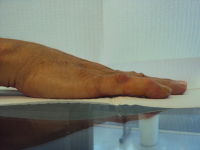

Clinical Example: Dupuytren Distal Interphalangeal Joint Needle Fasciotomy

Dupuytren contracture usually involves the metacarpophalangeal and proximal interphalangeal joints, but occasionally affects the distal interphalangeal joints. This is usually accompanied by proximal interphalangeal joint involvement. This is almost always a lateral rather than a central cord, and may present as a spiral cord, the neurovascular bundle superficial just proximal to the distal interphalangeal joint.

The functional impact of this is that it contributes to the fingertip catching on things like a hook. Isolated interphalangeal joint contractures in the context of hyperextensible metacarpophalangeal joints allow patients to defer evaluation until the contracture is severe.

The most common method of treating this is with fasciectomy, but needle fasciotomy may be effective. Collagenase has been used for this, but is an off-label application.

As with needle release or collagenase treatment of the proximal interphalangeal joint, recurrence is expected: these minimal procedures should be considered a temporizing step with expectations of partial improvement.

The following are examples of percutaneous needle fasciotomy for a variety of contractures involving the distal interphalangeal joint. Portals proximal and/or distal to the distal interphalangeal joint flexion creases are used, some bilaterally.

These are presented to illustrate the diversity of even this subset of Dupuytren disease. None had prior treatment.